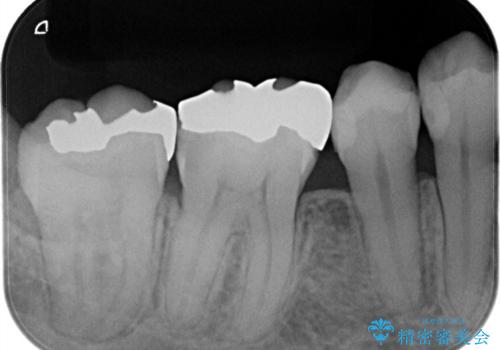

- 虫歯の治療を主訴に来院されました。

奥歯は不可逆性歯髄炎の診断のもと、根管治療を行なった後、被せ物の治療を行なっております。

根管治療を行なった歯は被せ物を使用することで、破折しづらくなります。